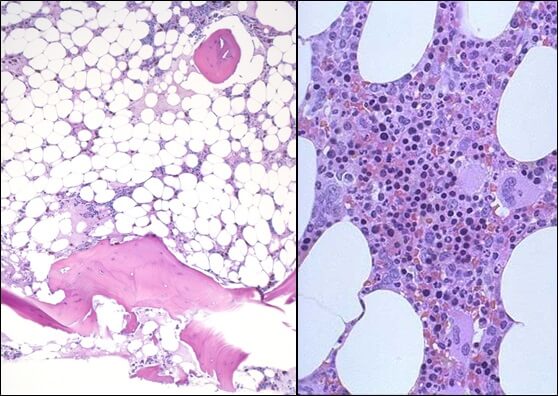

- Исследованиепунктата костного мозга. В миелограмме обнаруживается уменьшение количества миелокариоцитов и мегакариоцитов, снижение клеточности. В трепанобиоптате определяется замещение красного костного мозга жировым (желтым).

Привлекает внимание очень тяжелое течение этой формы у детей, картина носит острый характер и нередко смертельный исход наступает быстро. Гистологическое исследование выявило различную степень поражения костного мозга — от нормопластического аспекта вплоть до весьма тяжелой аплазии.

Гематологическая картина отражает наличие периферической панцитопении и нормоцитной или умеренно макроцитной анемий; показатель плодного гемоглобина бывает завышенным. При этом костный мозг представляется гипопластическим, жирным, иной раз нормо- или гипоцеллюлярным (Fanconi, Rohr Williams). Синдром видимо определяет рецессивный ген, в то же время цитогенетические исследования выявили большое разнообразие структурнохромосомных сдвигов (Bloom и сотр.). Описаны случаи, преобразовавшиеся в дальнейшем в острую лейкемию (Wintrobe).

Влияние на костный мозг тесно связано с количеством воздействующего на больного вещества. Исходно отмечается раздражение костного мозга и общая, в частности эритроидная, гиперплазия, сопровождающаяся лейкоцитозом, нейтрофилией и отклонением влево в периферической крови; затем, постепенно, развивается костномозговая гипоплазия с обширными участками жирного преобразования, наличием редких миелоидных элементов, выраженной реакцией лимфатической или плазмоцитной ткани, а в отдельных случаях моноцитной реакцией, которую часто нелегко различить от лейкемического поцесса (Мунтяну).